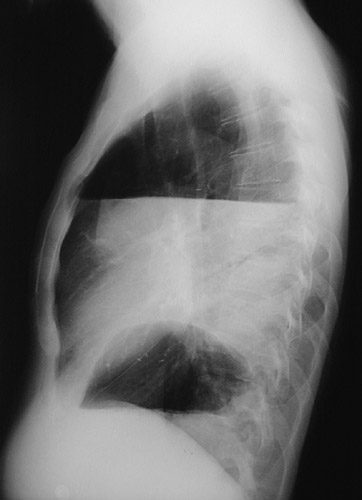

The chest radiograph here in lateral view demonstrates a large pleural effusion postoperatively following a left pneumonectomy.